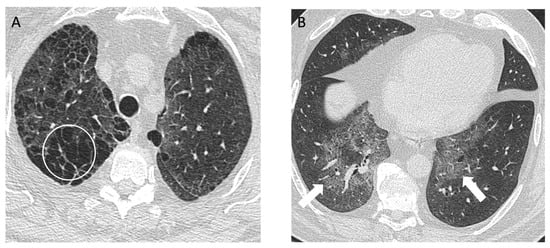

Figure 5.

A 43-year-old non-smoking male with 15-year history of tungsten carbide exposure as a metal grinding tool maker, diagnosed with hard metal lung disease, which was confirmed with surgical lung biopsy. (A,B) Axial computed tomography images demonstrate patchy ground glass opacities (arrows) and small centrilobular nodules (white circle) with minimal architectural distortion and traction bronchiectasis; (C,D) computed tomography images 18 years later demonstrate long-term evolution of fibrosis, with development of traction bronchiectasis (white circle) and mild honeycombing (black arrows) on the background of ground glass opacity and coarse reticulation; (E) posteroanterior view and (F) lateral view chest radiographs show a perihilar and lower lung zone predominant reticular abnormality (black arrows); (G) posteroanterior view and (H) lateral view chest radiographs 18 years later demonstrate a reduction in lung volumes, and the prior interstitial opacities appear coarser and more prominent, particularly in the perihilar lung (white arrows).